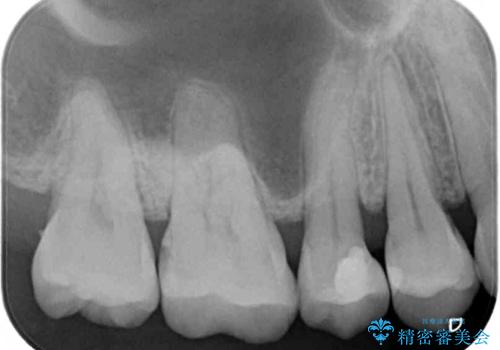

- 以前詰め物をした奥歯に物が頻繁に挟まるとのことで来院された患者様です。

充填物は形態が不正であり、歯肉付近にバリのように充填材料が飛び出していたため、歯肉が腫れやすい状態でした。

精密に治療を行うため、型取りを行った上でセラミックインレーによる修復治療を行うこととしました。